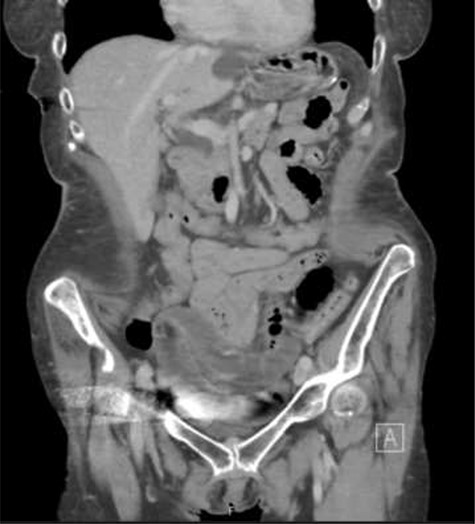

On physical exam, she was afebrile and normotensive. Her abdomen was soft with tenderness to palpation in the suprapubic region. Laboratory data demonstrated a white blood count of 7,200, a hemoglobin of 13.2, and a hematocrit of 39.3 percent. Renal function, electrolytes, liver function, and urinalysis were all within normal ranges. A CT of the abdomen and pelvis with intravenous contrast was obtained and revealed distended fluid-filled loops of small bowel mostly within the pelvis. There was evidence of some wall thickening and perienteric fat stranding. A transition point was felt to be within the pelvis (Figs 1 and 2).

Coronal slice of the CT of the abdomen/pelvis demonstrating distended fluid-filled loops of small bowel mostly within the pelvis. The transition point was identified in the pelvis.